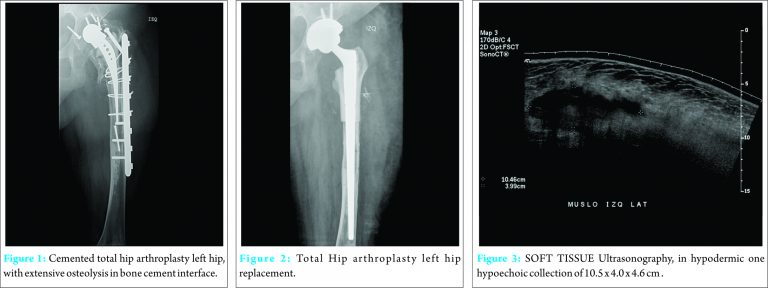

A female patient of 63-year-old presented to our orthopaedic department with prosthetic loosening of the isoelastic stem (Fig. 1), also femur and acetabulum with massive osteolytic defect performed by modular aloprosthesis of proximal femur and acetabulum of tantalum, and metal on polyethylene pair of friction (Fig. 2). Patient had good clinical evolution with the drain removed at the first postoperative day with output of 100 cc. serohematic. Patient was discharged in good condition on the fifth postoperative day. Five days later, patient was re-admitted to the emergency room for increased volume in relation to wound without infectious signs. The blood inflammatory parameters are normal. Soft tissue ultrasonography subfascial evidence seroma with estimated volume of 500 cc is taken. (Fig. 3). To avoid superinfection of a large extent surgery, it was decided to make an early cleaning surgery, in order to drain and take tissue samples and fluid culture. A collection is located under muscle planes adjacent to the aloprotesis, with communication between up fascia lata muscleplane. After the cleaning surgery and drainage, equally the seroma is maintained for 5 days with daily output of 200 cc of serous fluid. It was decided to perform a new scouring, with obliteration of third space, massage and Compression bandages. Negative cultures were obtained. Given the persistence of seroma, a literature review was undertaken to obtain therapeutic alternatives. Finally, surgical cleanliness was performed with resection of pseudocapsule seroma with curettage, making crops and application of 2 g. erythromycin diluted in 200 cc.of 0.9% saline solution. Customary closing was performed flat leaving a aspiration drainage N° 9 undert he fascia, which was measured daily. The next day, the drainage measured serohematic liquid 100cc, and 60cc was measured on the 2nd day. On the 3rd day, 10 cc of liquid was measured, and the drainage was removed on the 4th day. Subsequently, the patient was discharged in good condition without signs of infection, tension, edema or collection in the thigh wound.